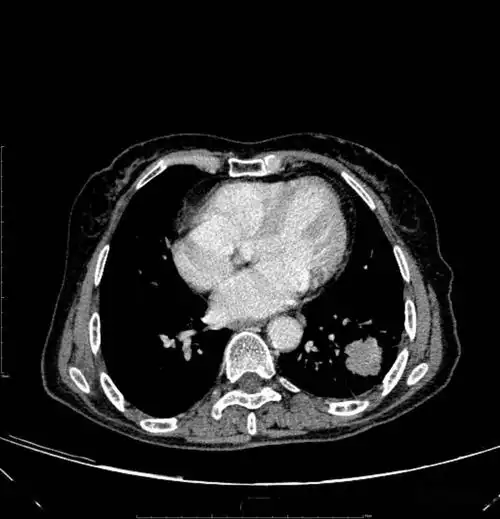

【读片】肺癌? [病例帖]

胸部ct平扫示左下肺占位肺癌